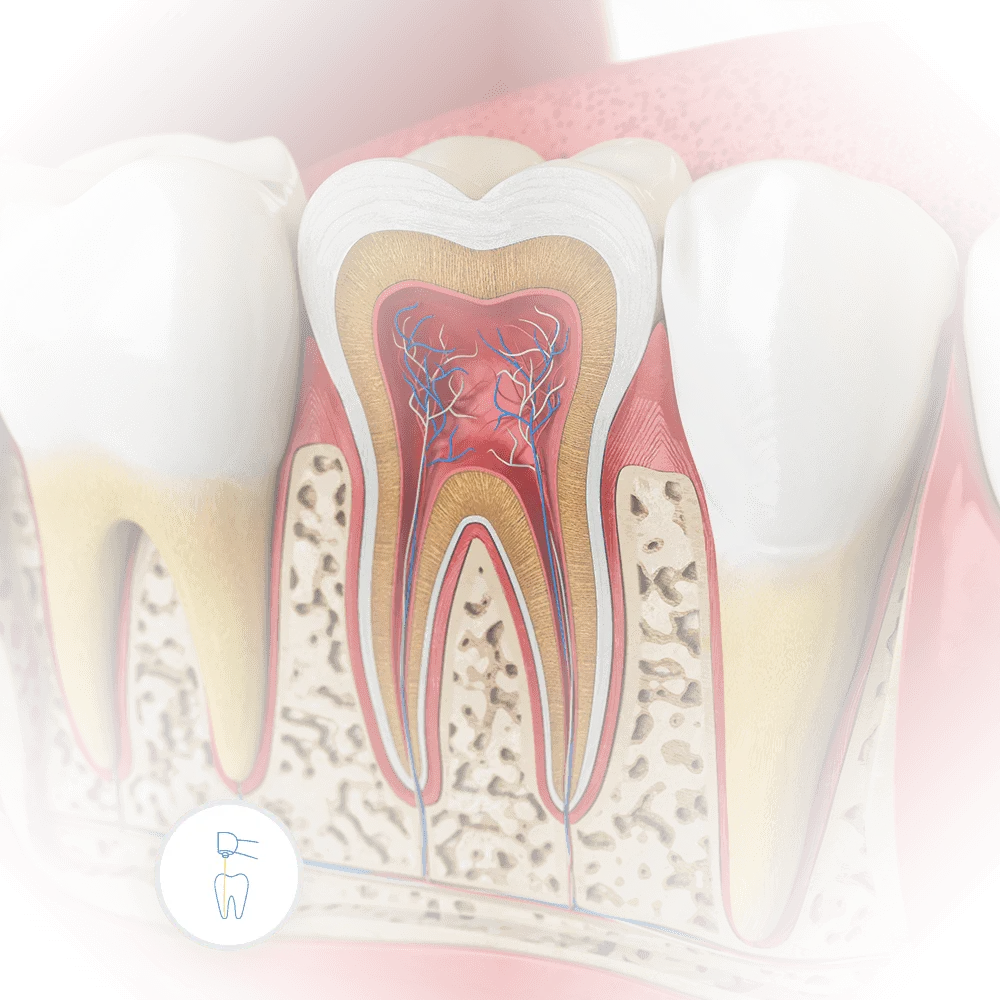

anatomy of a tooth with relation to dental endodontic root canal procedure

Root Canal

When a tooth is damaged or infected, a root canal can save it. At Vartanian Dental Group, we offer precise and gentle root canal procedures, ensuring your comfort and preserving your natural teeth.